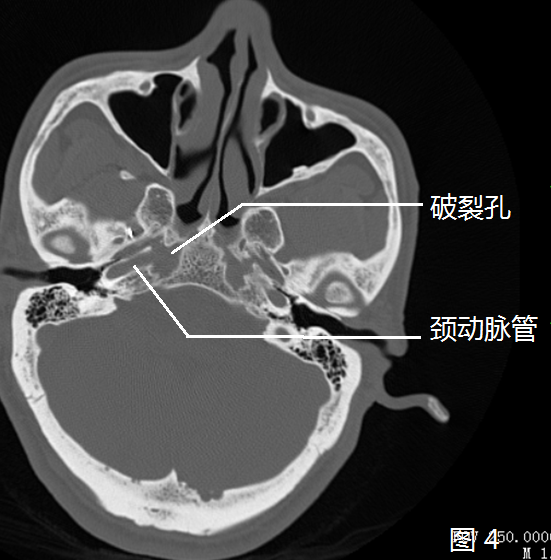

因此,从颅骨解剖上看,"颈动脉管升段"和"破裂孔"是一体的,解剖学把